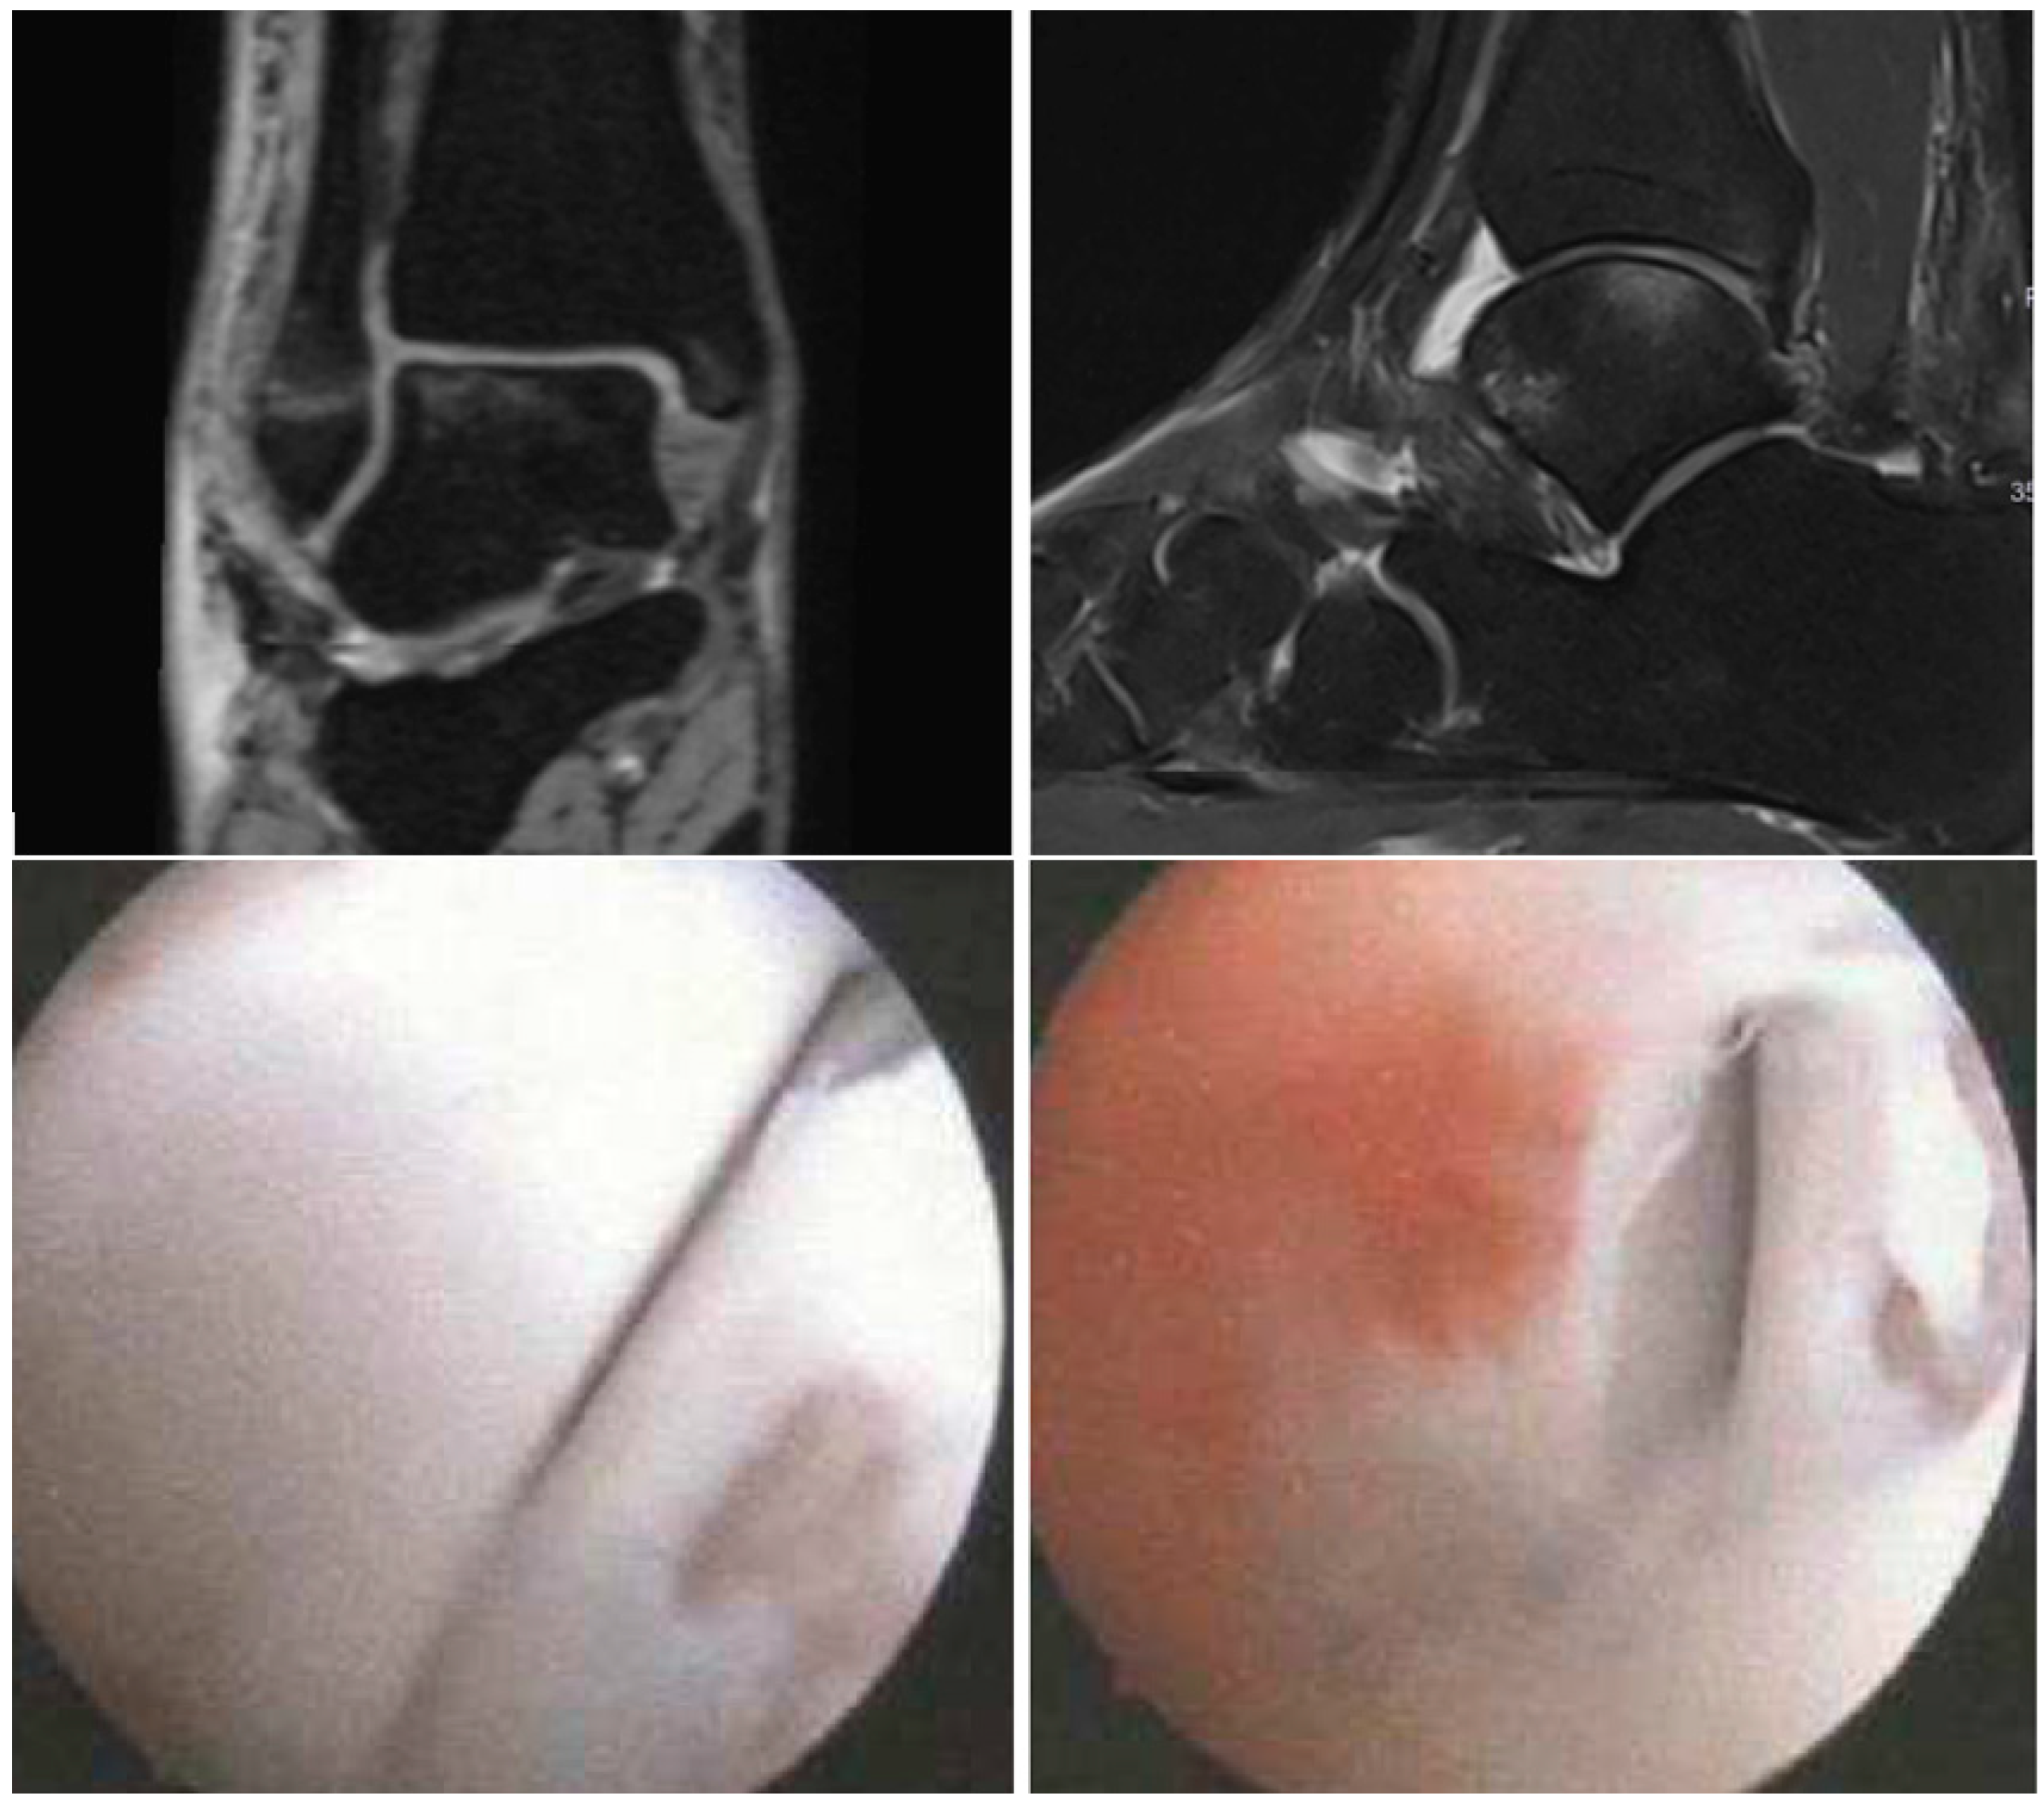

2.3. Arthroscopic Evaluation

2.4. Assessment of Chondral Lesions

3.2. Evaluation of the Intraoperative Arthroscopic Findings

3.3. Validation